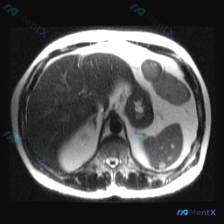

今天看到一份腹部MRI的T2WI图像,焦点在脾脏,整理一下读片的思考过程,避免踩坑。 先看核心影像表现 这是一张轴位T2WI,最突出的异常在脾脏: - 信号:脾实质内有数个类圆形极高信号影,信号强度接近脑脊液,提示是液体(浆液性为主)。 - 形态:边界清晰,但边缘呈分叶状,囊腔之间相互融合或紧邻,不...

整理了一份腹部囊性病变的影像资料,结合影像分析报告梳理下思路: 影像核心表现(T2加权轴位) - 肝脏:信号无明显弥漫或局灶异常 - 脾脏:可见类圆形多房性囊性病灶,边界清晰,T2呈显著高信号(符合囊液信号),无周围浸润或水肿带 - 上腹部额外发现:胰腺体尾部前方/胃后方,还有一个孤立的、边界清晰的...